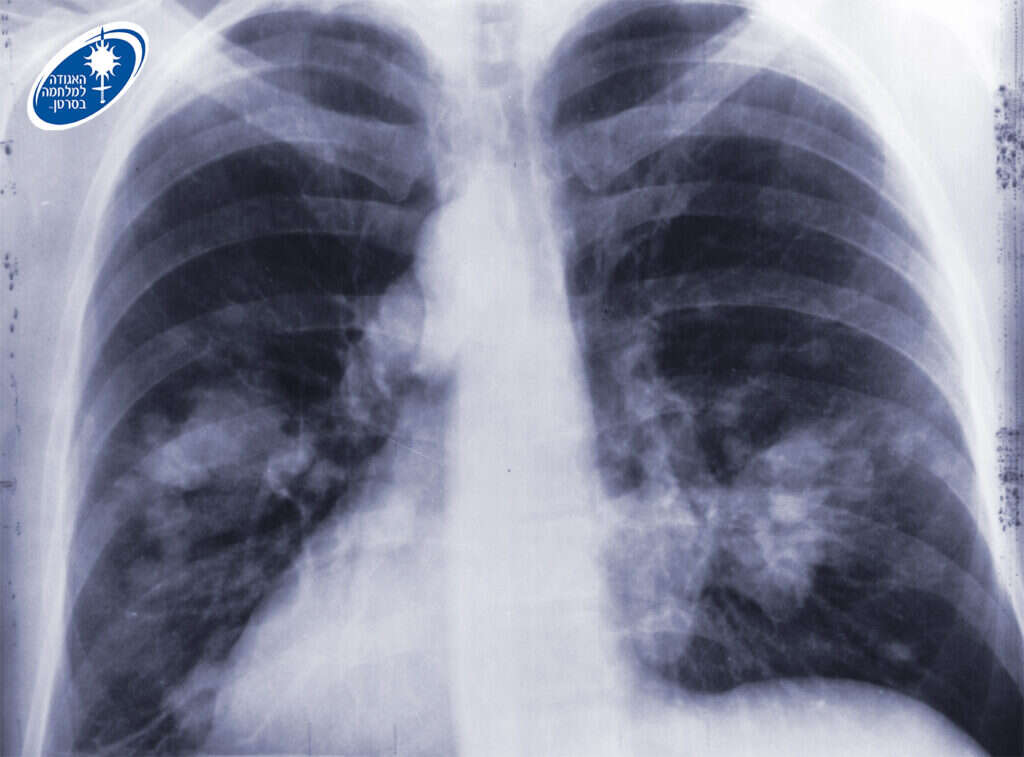

גם הפסקת עישון לאחר איבחון בסרטן ריאות עשויה להציל חיים. | צילום: רנטגן ובו ריאות אדם החולה בסרטן. באדיבות האגודה למלחמה בסרטן